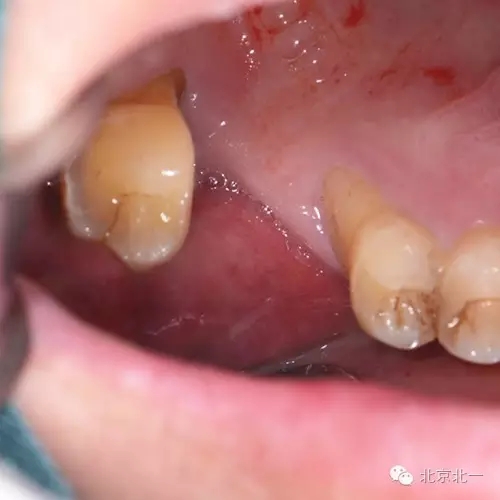

患者,男,30歲,右側(cè)上頜后牙區(qū)缺失,咨詢種植。

檢查:15、16 缺失。17三度松動。

圖一:手術(shù)前臨床照片